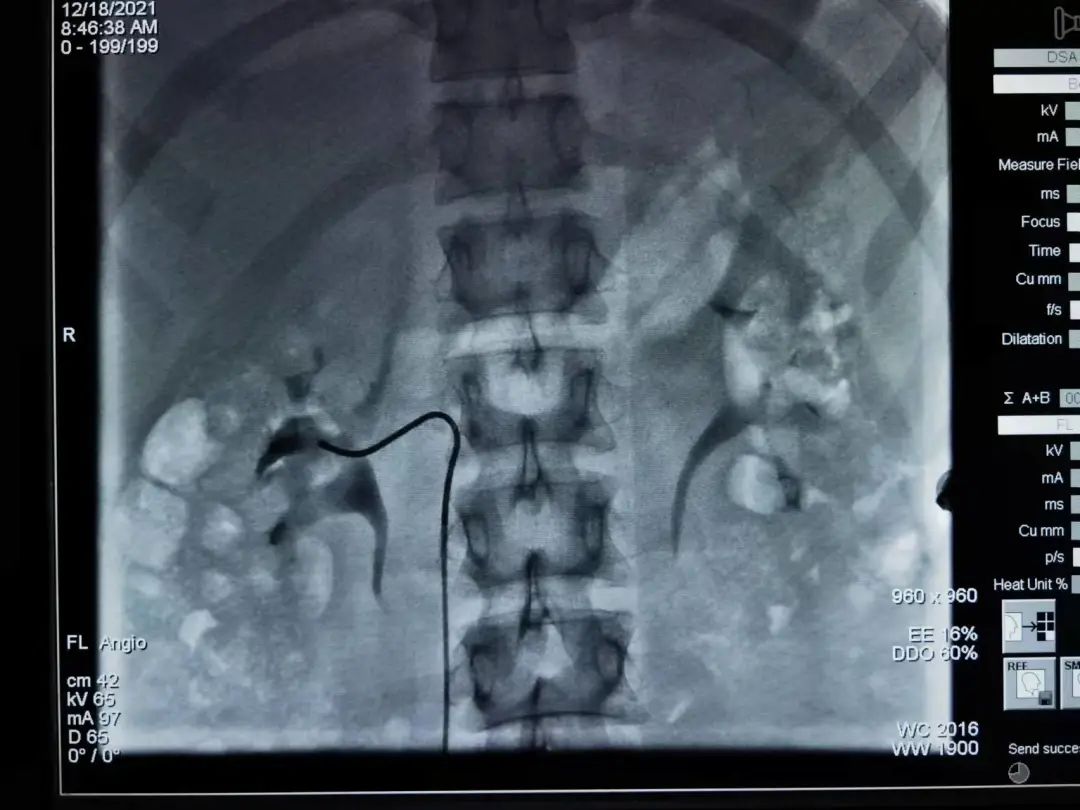

继发性高血压,也就是服用多种降压药也控制不好的疾病,大多是肾上腺疾病引起,而且此类疾病并不在少数。原发性醛固酮增多症,库欣综合征,嗜铬细胞瘤三大原因引起的继发性高血压甚至难治性低钾血症,因为激素水平分泌受各种因素影响,临床原因难查。内分泌科罗玲医师去年从南京鼓楼医院进修,专门学习了肾上腺AVS采血技术。回来后,已经有两位考虑肾上腺疾病的患者,和介入科黄主任一起,进行介入肾上腺AVS采血功能诊断。AVS采血技术临床激素水平精准度极高,有利于临床诊断,为患者下一步的诊治提供精确治疗。这项技术填补了淮南市的空白!